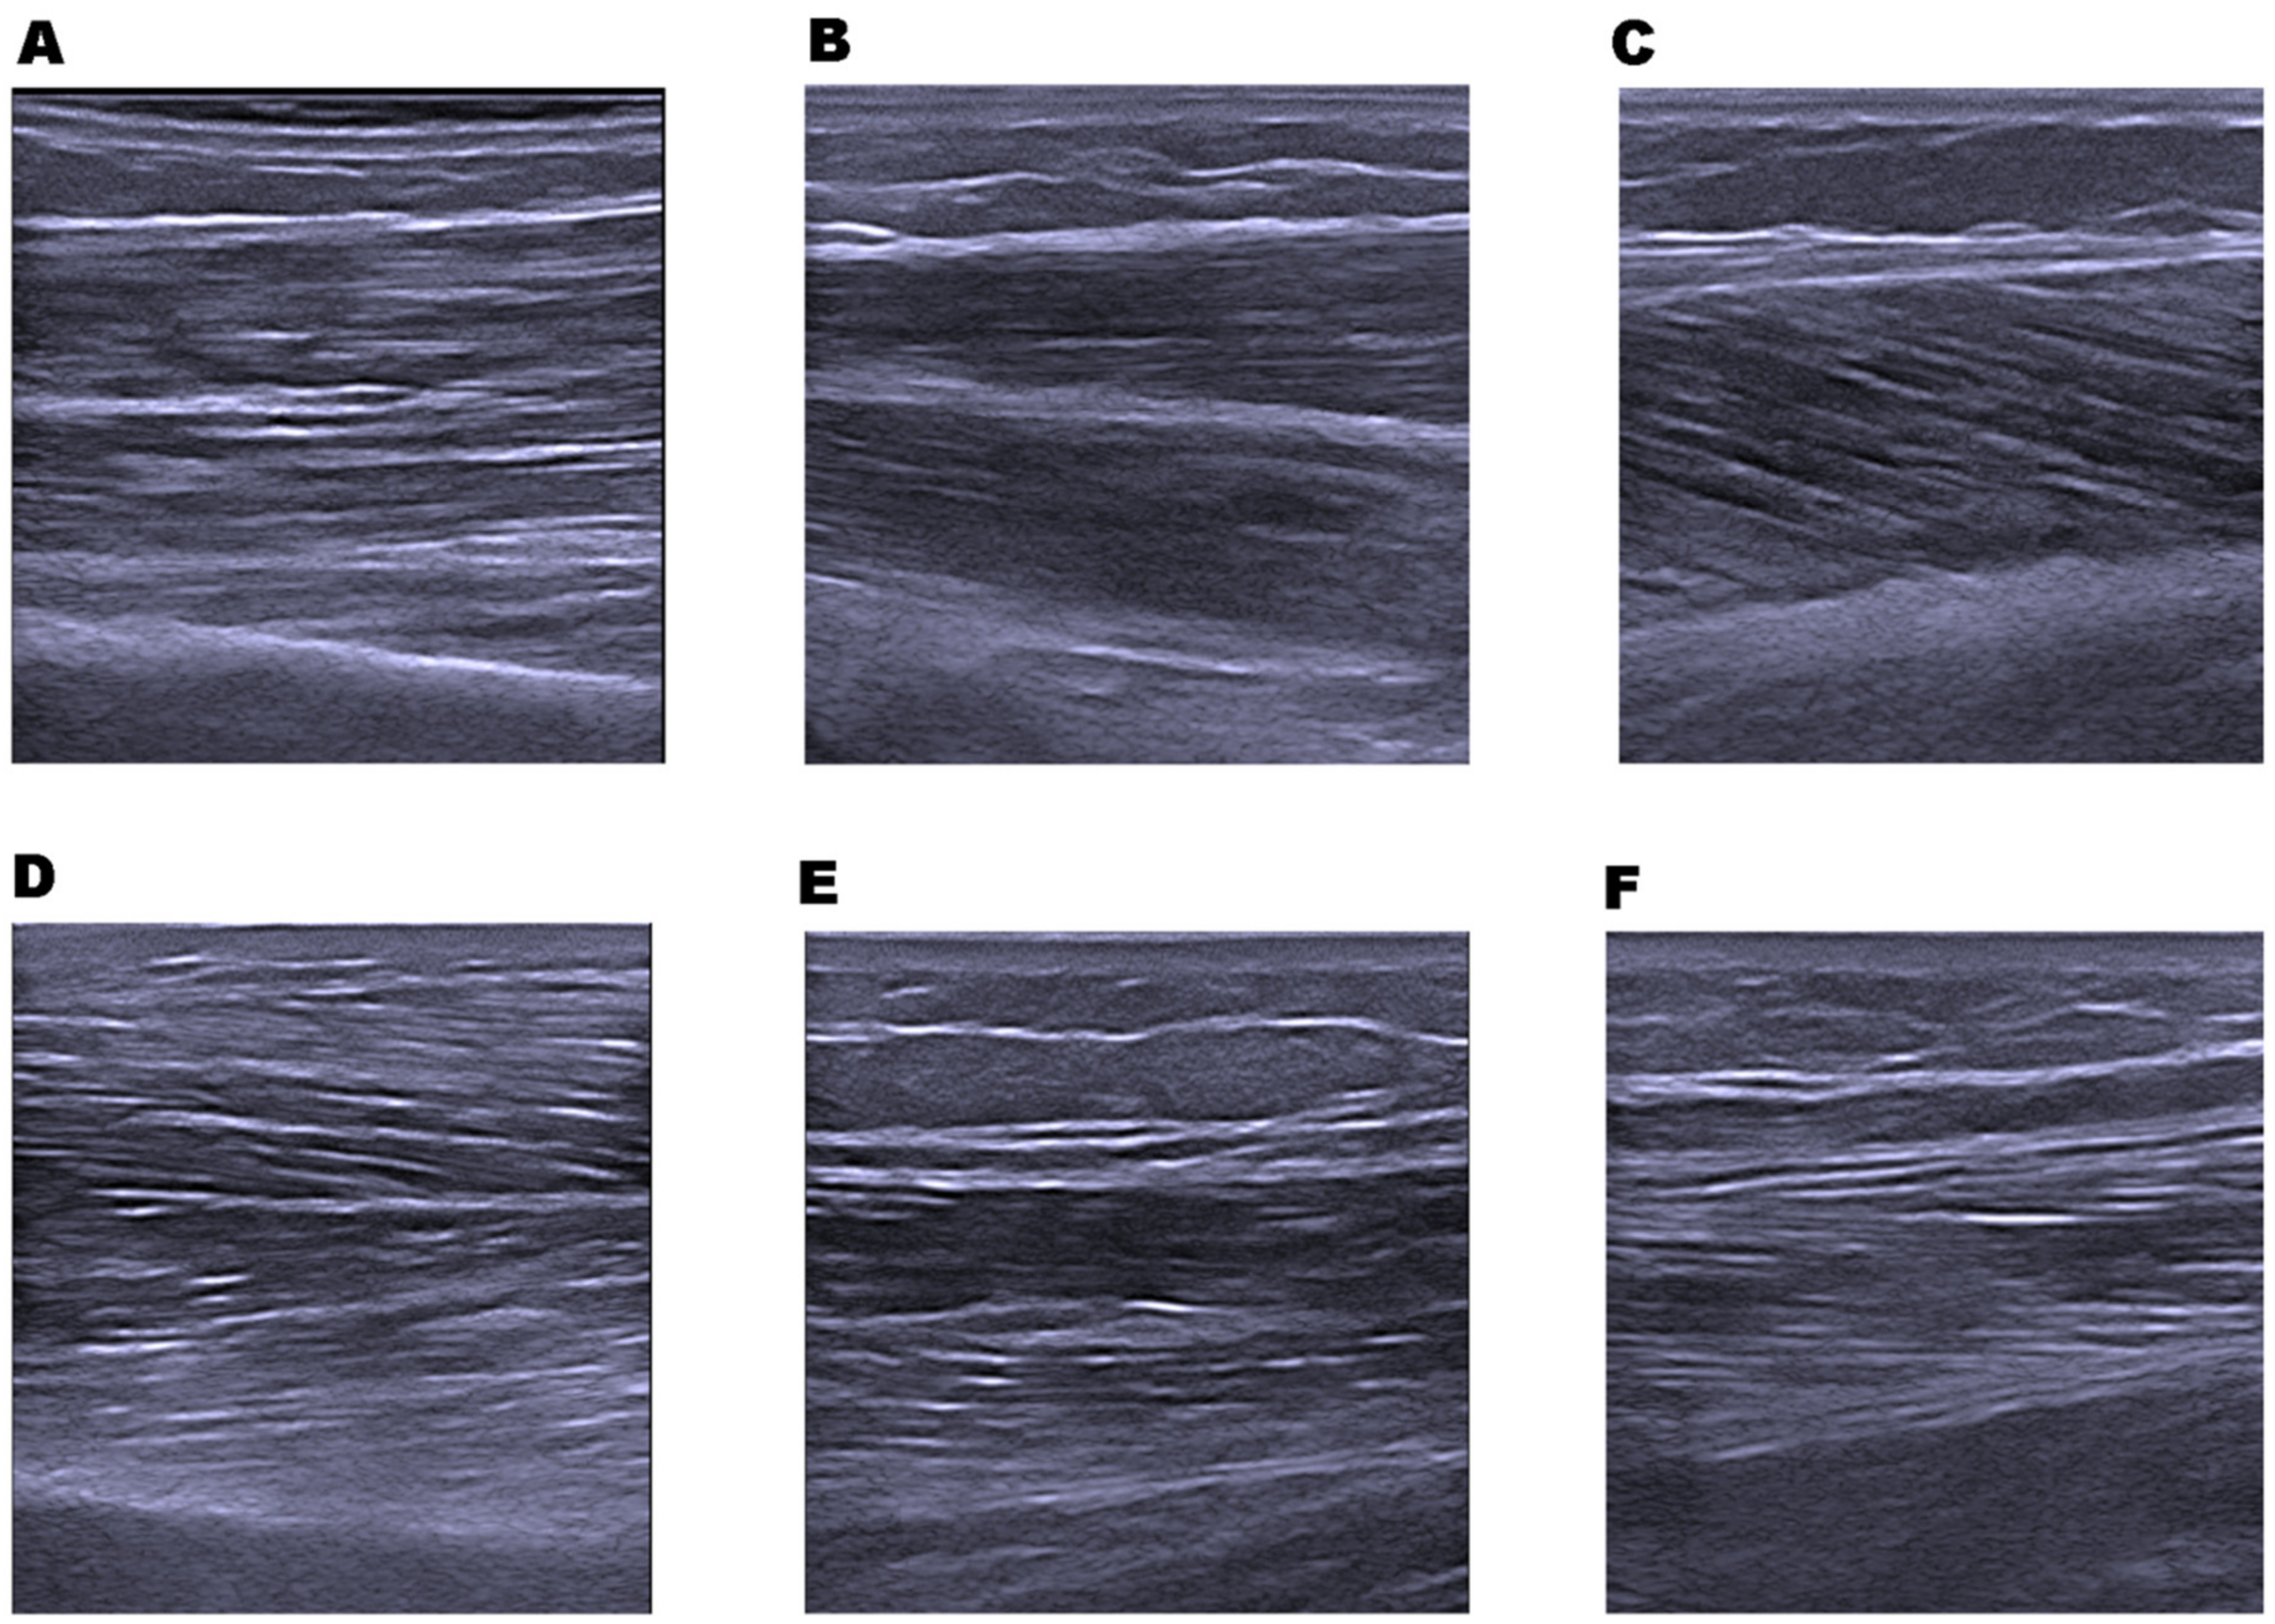

2.7. Muscle Architecture; Muscle Thickness and Echo Intensity